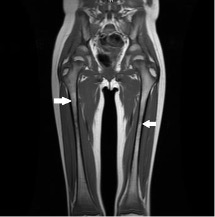

A 2-day-old boy was brought to the well-baby nursery with edema of the right thigh. There was no abnormality noted at birth.

12/31/2022